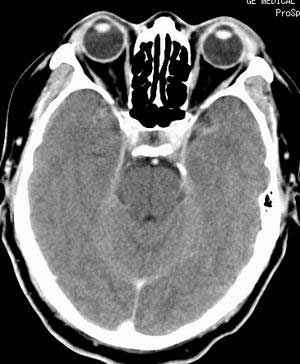

在平扫时,见右侧枕骨下方小脑半球表面带状模糊稍高密度影,考虑为耳源性脑内感染。

平扫右侧岩骨与枕骨交角内侧脑质内见淡片状密度增高影,内缘清晰。增强图象上未见明显显示。

右枕颅骨内板下高密度应该是窦的变异,和其症状应该无关,根据病史另找原因吧。[em16]

条状高密度为小脑幕吧

正常平扫片,右侧为血管影。

条状高密度为小脑幕

横窦乙状窦。

增强的横窦乙状窦。